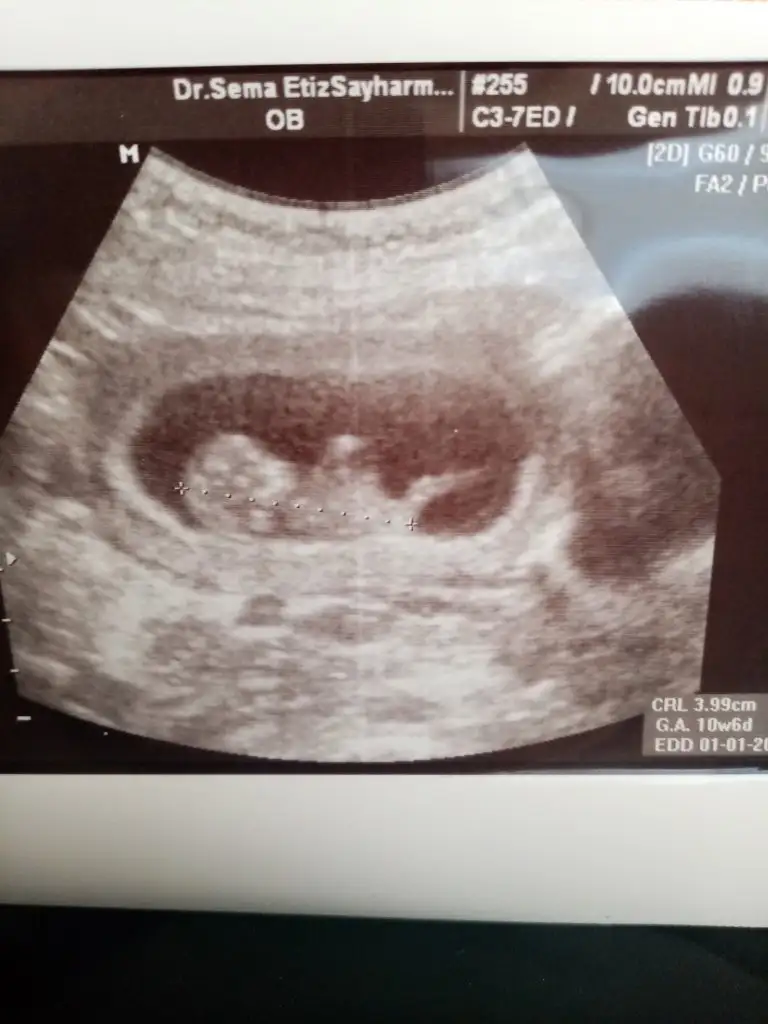

Kizlar yorumunuz

Eklentiler

• 70733DC5-F775-414D-9BD5-CCA598AFA0FF.webp